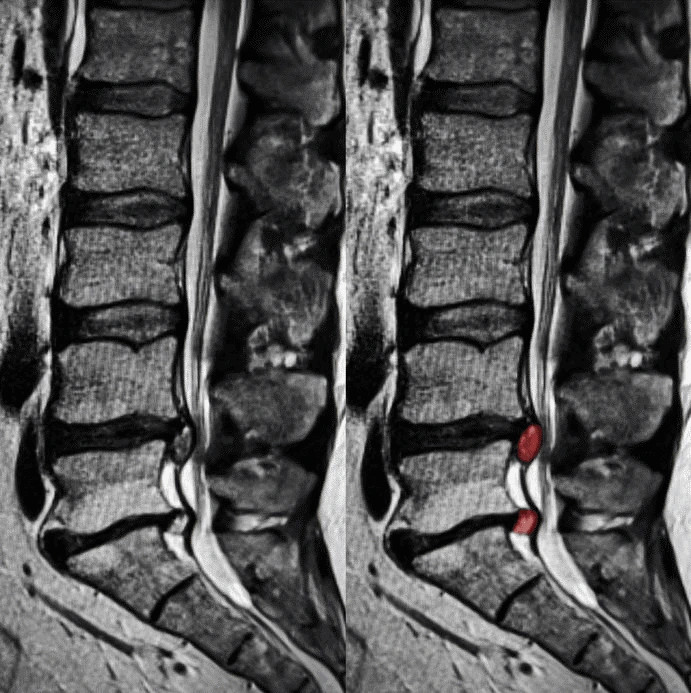

An intervertebral disc lies between the bones (vertebrae) of the spine and acts as a cushion and shock absorber. In a bulging disc the outer rim of the disc (the annulus) protrudes outward but remains intact; in a herniated disc the inner gel‑like core (nucleus) pushes through a tear or weakness in the outer rim.

Chiropractors often see patients with these disc‑issues. Understanding whether the disc is simply bulging (less severe) or herniated (potentially more symptomatic) helps in triage, conservative management (e.g., manual therapy, postural correction, exercise) and referral decision‑making.